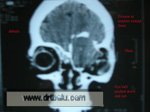

CT scan of the patient clearly showed the swelling over left frontal sinus with erosion of the outer and inner tables. The mass is also seen to extend into the frontal lobe of the brain.

Coronal CT PNS showing left frontoethmoidal mucocele